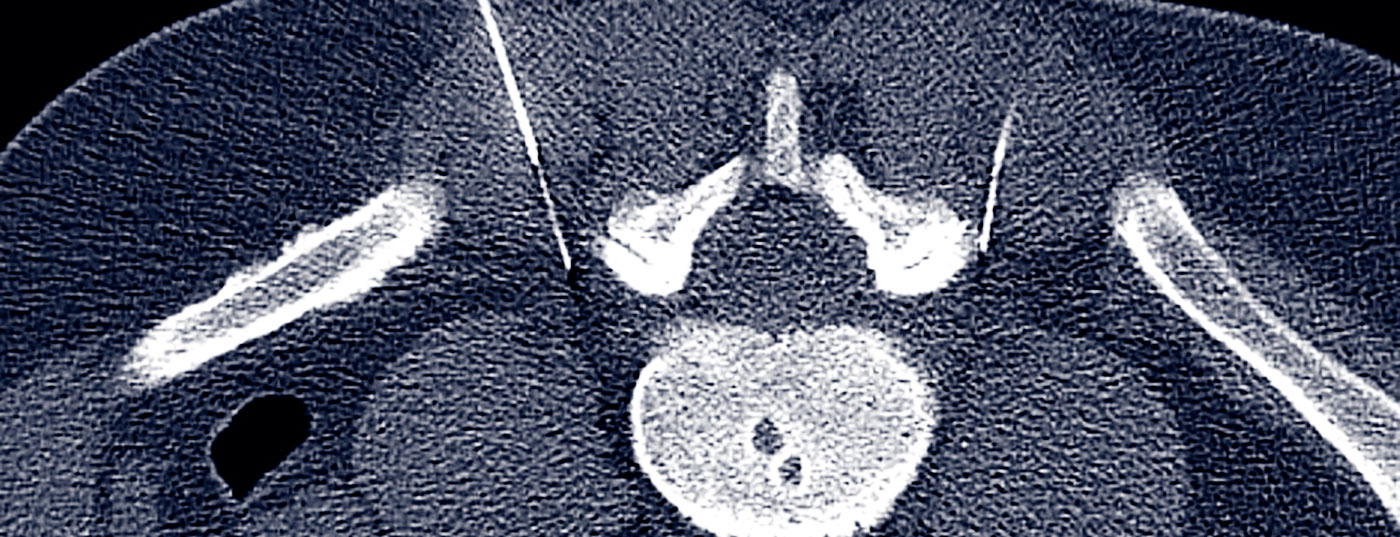

Die CT-gesteuerte PRT hat sich zu einem anerkannten minimalinvasiven Schmerztherapieverfahren an der Wirbelsäule entwickelt. Sie ist ein effizientes, risiko- und nebenwirkungsarmes, ambulant durchführbares Verfahren. Mit durchschnittlich 3 bis 5 Behandlungen in etwa dreiwöchigem Abstand lässt sich bei etwa 80% der Patienten eine lang anhalte relevante Schmerzreduktion oder Schmerzfreiheit erreichen.